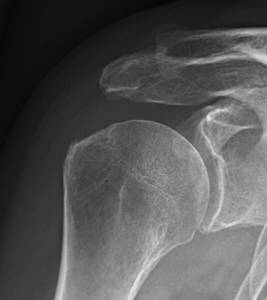

Radiologiske tegn til impingment (sklerosering og osteofytdannelse), både på acromion og tuberculum majusområdet.

Operationsteknikken sigter på at lave en plan flade på undersiden af

acromion(type 1 acromion).